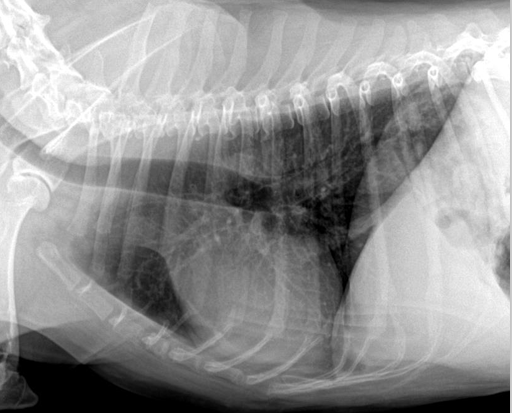

| Inspiration | Expiration |

|---|---|

![]() | ![]() |

| - 폐 부분이 더 opaque (뿌얘보임) | |

| - 횡격막이 더 위로 올라와 심장과 붙어 있음. |